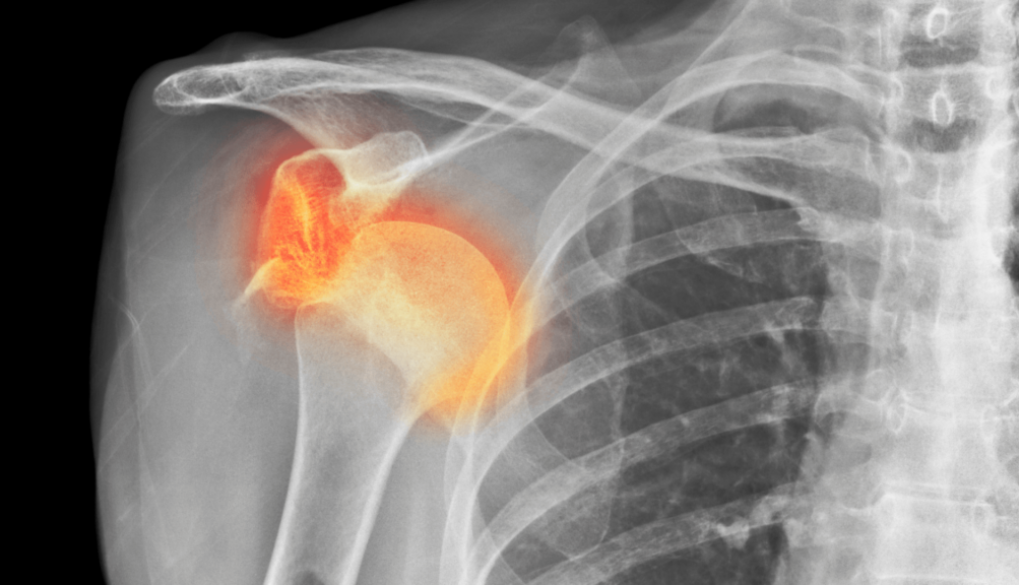

Von allen Gelenken im menschlichen Körper, die auskugeln, ist die Schulter bei weitem das häufigste. In 50% aller Gelenke, die auskugeln, ist es die Schulter. Das ist aber nicht verwunderlich, wenn man bedenkt, dass die Schulterpfanne eigentlich gar nicht so groß ist. Eine Schulterauskuglung wird in der Regel durch eine von drei Ursachen ausgelöst:

Verglichen mit der tiefen knöchernen Hüftpfanne ist die Schulterpfanne eher als kleine Schale zu bezeichnen. Diese Schale wird durch das Labrum noch verstärkt. Das Labrum ist einen Knorpelring, der direkt an der Gelenkpfanne der Schulter ansetzt. Das Labrum ist wiederum mit den Muskeln der Rotatorenmanschette verbunden, die zusammen die Schulterkapsel bilden. Sie sollten diese Muskeln als eine dynamische Gelenkpfanne betrachten, die zur Stabilisierung des Schulterkopfes beiträgt, indem sie genau im richtigen Moment angespannt wird, wenn sie ihre Bewegungen ausführen.

Für die Anforderungen, die wir an die Schulter stellen, ist ihre Anatomie sehr sinnvoll. Die minimale Gelenkpfanne ermöglicht es uns, den Arm frei in allen Richtungen zu bewegen. Durch diese Bewegungsfreiheit wird die Stabilisierung der Schulter für den Körper jedoch schwieriger.

In einigen Fällen können bei einer traumatischen Schulterluxation mehrere Strukturen beschädigt werden. Zunächst kann einmal das Bindegewebe der Kapsel und/oder des Labrums gedehnt werden oder reißen. Zum anderen kann sich eine knöcherne „Bankart-Läsion“ entwickeln, bei der es durch den Aufprall zu einer Fraktur am unteren Ende der Schulterpfanne kommt. Dies geht häufig mit einer „Hill-Sachs-Läsion“ einher, einer Delle in der Schulterkopf selbst. Eine Röntgenaufnahme der Schulter kann dies entweder zeigen oder ausschließen.